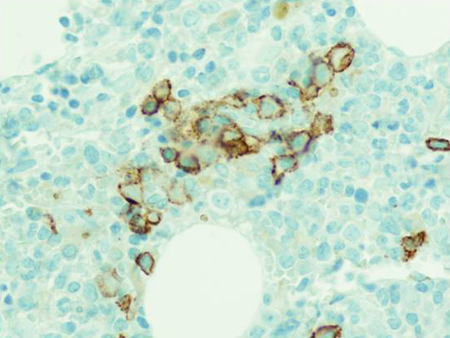

Monoclonal gammopathy of undetermined significance

CD138 immuno-histochemical staining highlighting small clusters of plasma cells

From the collection of Ola Landgren, MD, PhD